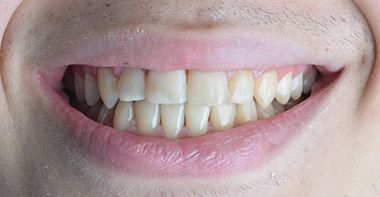

Firstly, we treated the gap between the teeth with Invisalign. We also corrected the angle of the front teeth. Invisalign Lite was enough. Glenn visited Turkey 4 times in a period of 8 months. During his last visit, we replaced the old fillings in his front teeth with composite bonding. We performed lingual retrainer to maintain the alignment of the teeth. We produced an sx plate for him to use at night and delivered it to him. Glenn was very happy. He said he wanted to study at a dentistry faculty.

Dr Berra performed my orthodontic treatment. I was comfortable with clear aligners, we thought it would look better than braces. Thank you very much to the Cure Voyage team and Dr Berra.